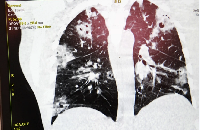

Изучение проблемы низкого качества рентгенограмм на Вашем оборудовании.